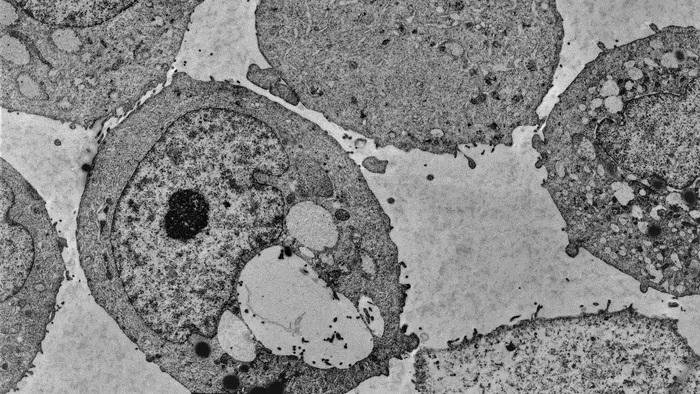

Когато на мишки с рак на простатата се дава менадион, той нарушава процесите на оцеляване на рака. Екипът на Тротман открива, че менадионът убива клетките на рака на простатата, като изчерпва липид, наречен PI(3)P, който работи като идентификационен етикет. Без него клетките спират да рециклират входящите материали и в крайна сметка експлодират.